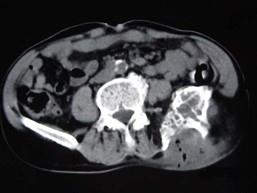

问题 患者,女性,68岁,近2年来感左髋部疼痛,活动后加重,2周前由于剧烈运动后左下肢活动不能,查体左髋部压痛明显,皮肤稍显红肿,请结合所提供的图像,选择最佳选项 ( )

选项 A、转移瘤 B、软骨肉瘤 C、骨巨细胞瘤 D、动脉瘤样骨囊肿 E、骨囊肿

答案 D